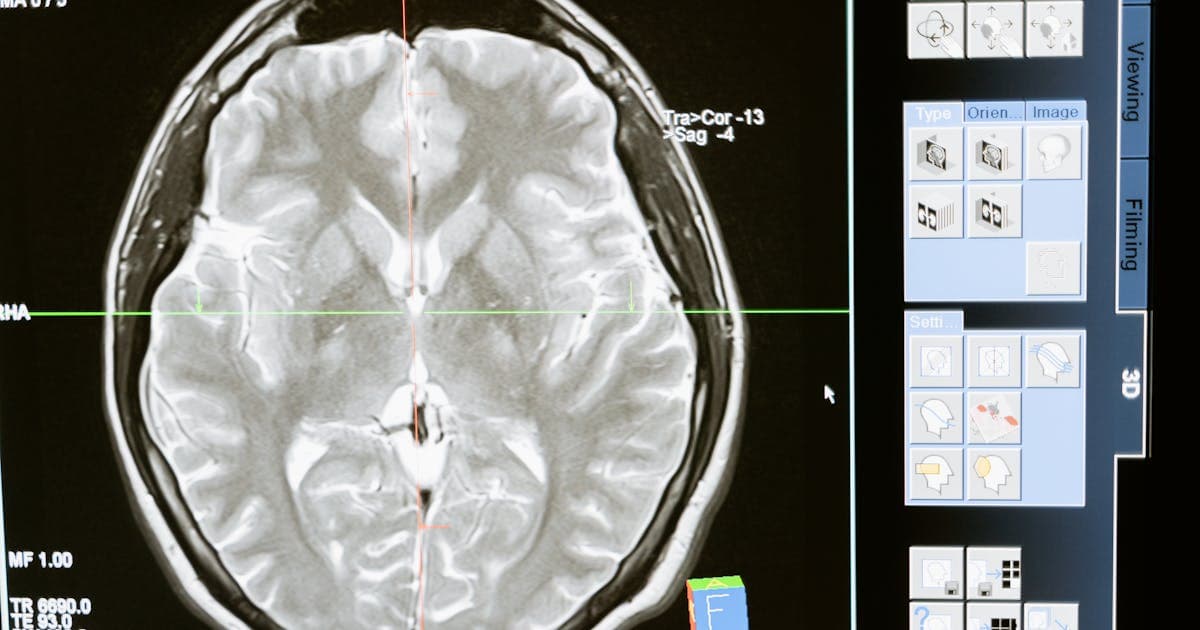

診断用画像機器を専門とする日本の医療機器メーカーより、胸部X線画像の異常を事前スクリーニングするAIアシスタント開発のご相談をいただきました。